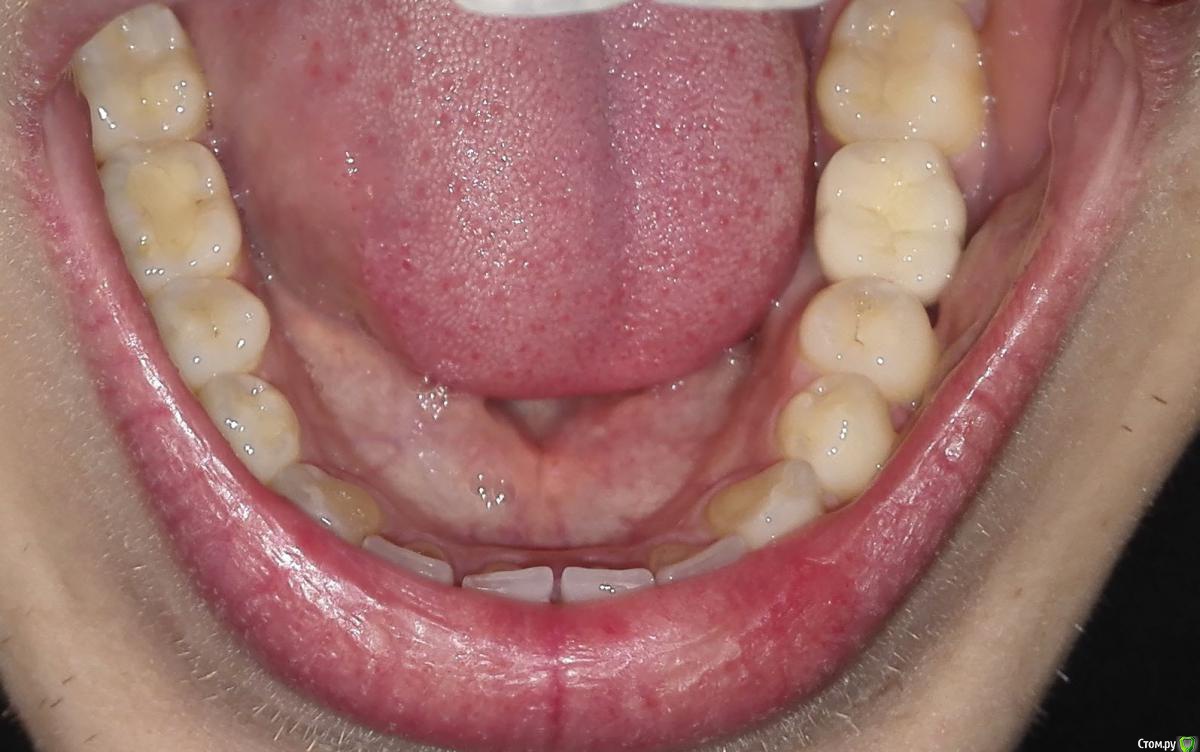

Friend Опубликовано 24 марта, 2015 Поделиться Опубликовано 24 марта, 2015 Добрый день, друзья! Оцените, пожалуйста, работу врача по установке коронки (на имплант).6 зуб, справа. И какие будут последствия, если остваить всё как есть? Ставят уже второй раз... Ссылка на комментарий

Friend Опубликовано 25 марта, 2015 Автор Поделиться Опубликовано 25 марта, 2015 Дмитрий, проблема в том, что коронка несколько криво установлена. Ссылка на комментарий

johniola Опубликовано 25 марта, 2015 Поделиться Опубликовано 25 марта, 2015 (изменено) коронка установлена с учётом вашего прикуса.всё нормально,не надо искать проблемму там,где её нет Изменено 25 марта, 2015 пользователем johniola 3 Ссылка на комментарий

Friend Опубликовано 25 марта, 2015 Автор Поделиться Опубликовано 25 марта, 2015 Ещё одни нюанс. Изначально она стояла ровно, однако, через какое-то время сместилась. Установлена на постоянный цемент. Из-за чего это произошло?Оставить всё как есть или переделывать? Ссылка на комментарий